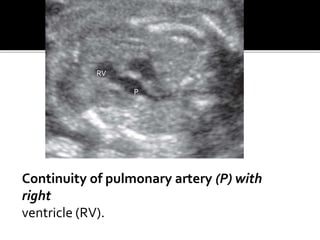

Continuity of pulmonary artery (P) with

right

ventricle (RV).

Continuity of pulmonaryartery (P) with right ventricle (RV). RV P